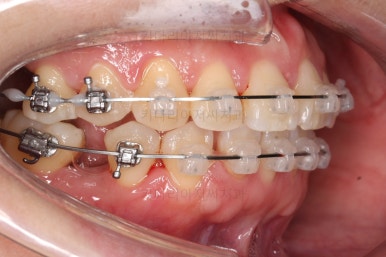

발치 공간을 적극적으로 줄여 나갑니다.

이 과정에서 입매, 앞니 각도, 정중선 등을 신경 써줍니다.

아무래도 상하좌우 비어 있는 공간의 위치가 모두 달랐기 때문에 자칫하면 중앙선이 한 쪽으로 쏠려버릴 수 있기 때문이죠.

중앙선 개선을 위해 미니스크류와 다양한 장치를 활용해 주고요.

발치 공간도 많이 줄었네요.

중앙선, 교합 등을 더 신경쓰고 마무리를 합니다.

마무리 전에 부산교정치과 충치치료도 깔끔히 진행하게 됩니다.